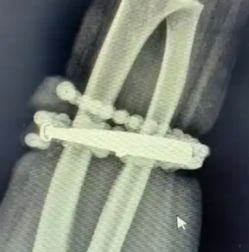

然而,就在两周前,龚女士的情况急转直下:手腕不仅疼痛加剧,还出现了明显的红肿,甚至有脓液渗出。她这才惊觉——手镯和串珠,已经有一部分“长”进了肉里,根本取不下来了!

“这是典型的首饰长期压迫、摩擦,加上细菌感染,引发的慢性炎症和肉芽组织增生。”医生介绍,此时,手镯和串珠已经成了一个不断刺激皮肤、污染伤口的“病灶”,如果不尽快手术取出,感染可能进一步扩散,甚至危及生命或影响手臂功能。

经过一个多小时的手术,医生们将手镯和串珠从厚厚的增生组织中完整剥离出来。目前,龚女士恢复良好,已顺利出院。